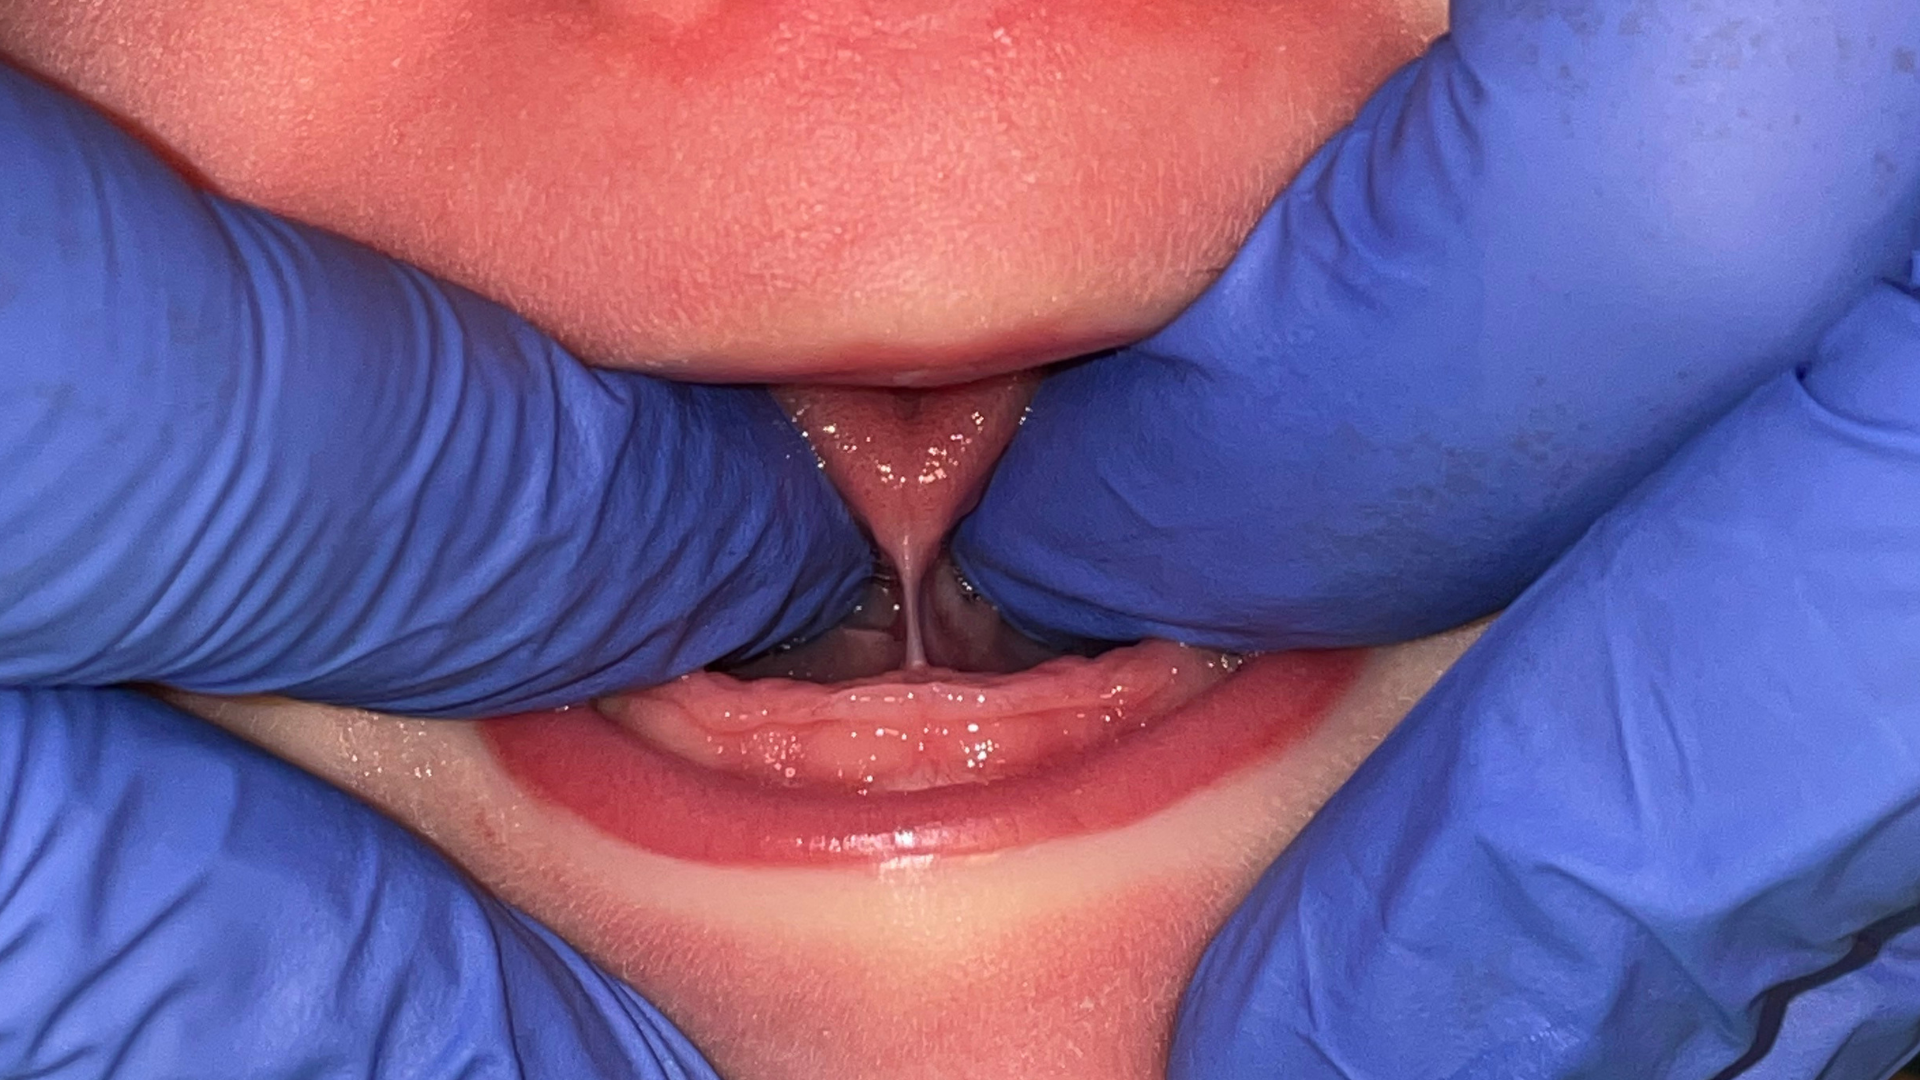

Lip Tie shown by Dr. Samira Jafari - Atlanta Airway Dentist

Lip Tie

A lip tie occurs when the tissue that attaches the gums to the lip is tight. This may make movement of the lips more difficult, leading to open mouth posture, difficulty with speech, or a gap between front teeth. In babies, a lip tie affects breastfeeding by making a deep latch more difficult.